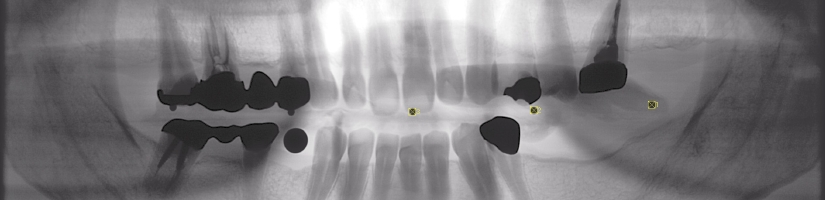

パノラマ写真(写真上)は一般的には全体像を見るのに適したレントゲンですが低解像度なために正確な診断のために追加撮影が必要でしたが、デジタル化によって高解像度化されているためそれだけで必要な情報を得ることができるようになりました。